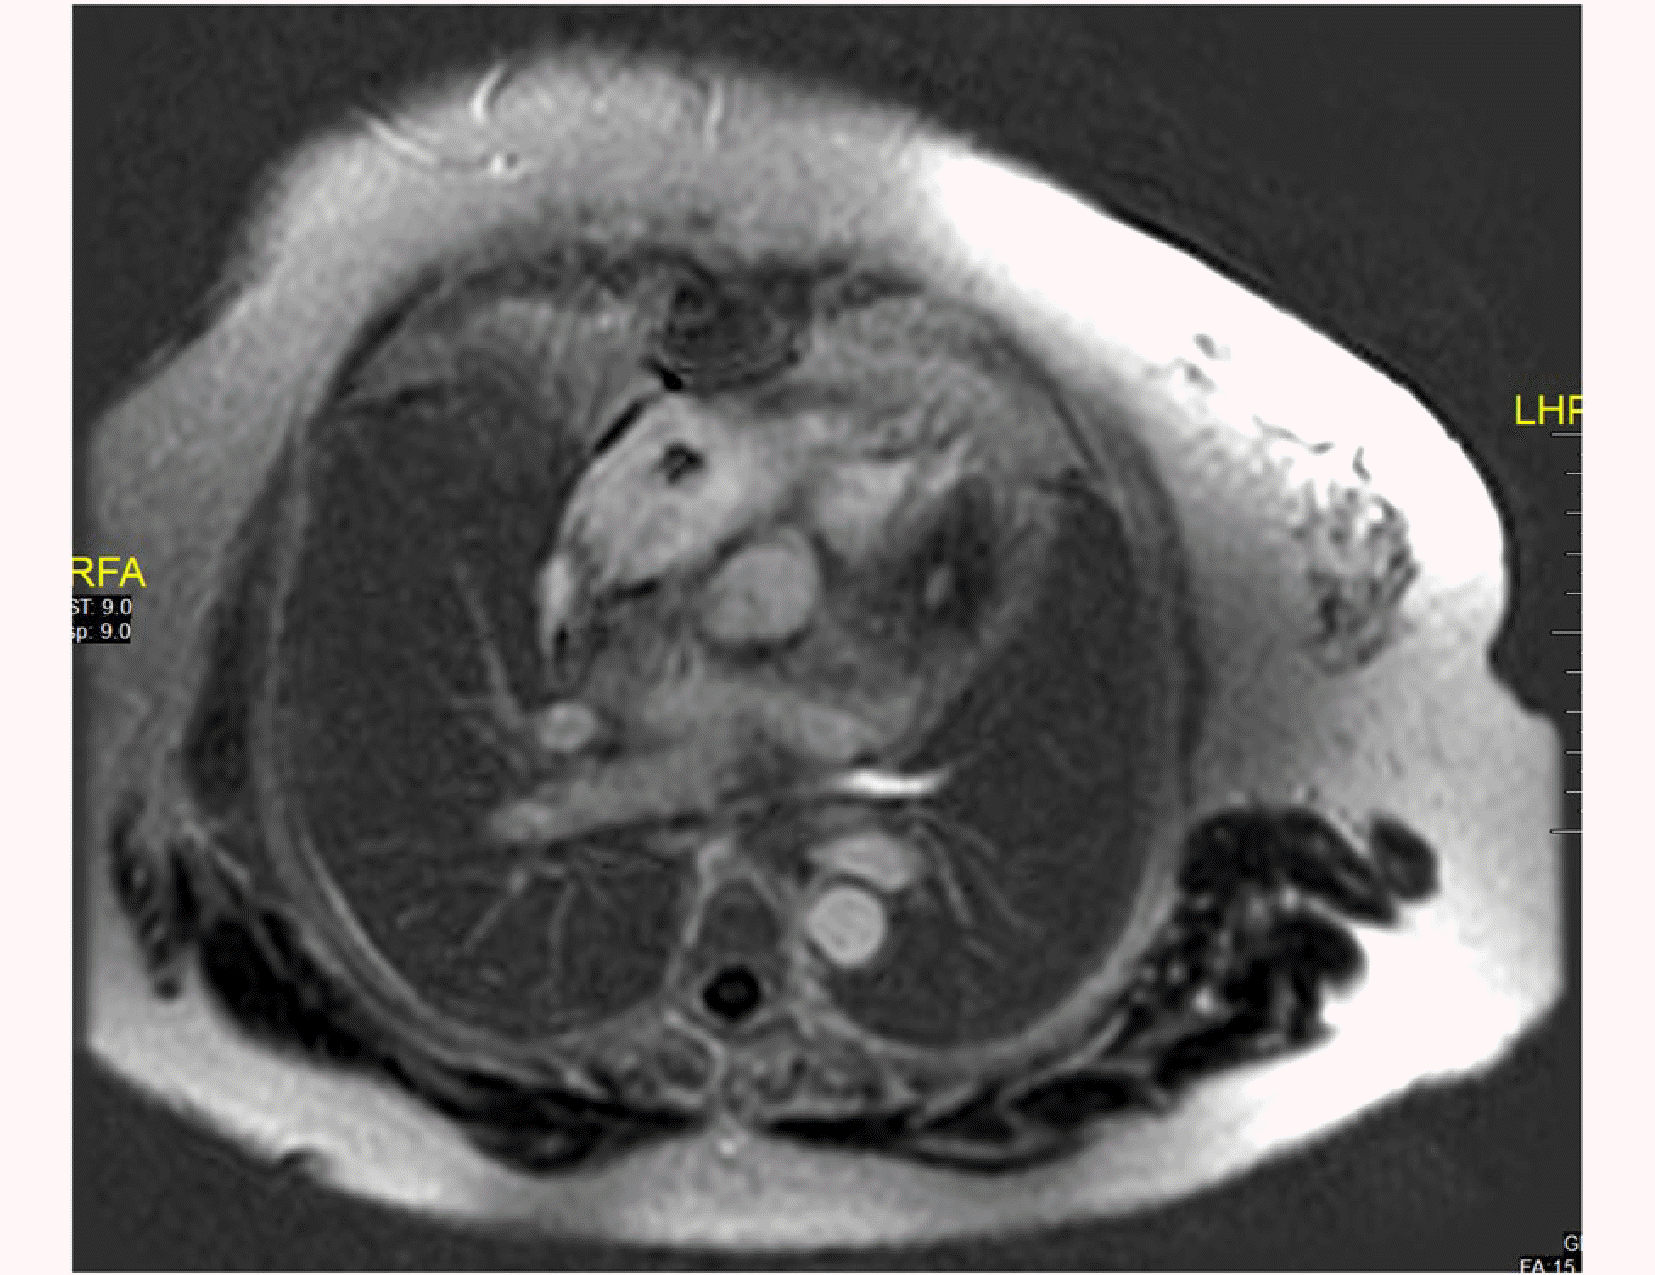

A 67-year-old female with known diabetes mellitus and hypothyroidism presented with off and on palpitations and swelling in the bilateral lower limbs for 1 year (left > right), associated with erythema. The patient was diagnosed with atrial flutter. A 2D echocardiography revealed soft tissue density along the pericardium. A positron emission tomography (PET) scan in October 2018 revealed a 10.2 × 7.7 cm mediastinal mass, sclerotic lesions in the bones, and a hypodense lesion in the thyroid. Cardiac magnetic resonance imaging (MRI) in March 2019 revealed a mediastinal mass of 11.3 × 7.9 cm, encasing her right atrium (Fig. 1). The biopsy showed aggregates of foamy histiocytes and was positive for CD68 and CD163, but negative for CD1a, S100, and B-RAF immunohistochemical staining. A somatic BRAF missense mutation with a V600E alteration in exon 25, with a mutant allele frequency of 4.9%, was detected along with an ASXL1 mutation. Fine-needle aspiration cytology of the thyroid lesion was unremarkable. ECD was diagnosed in March 2019. Vemurafenib was initiated at a dose of 240 mg twice daily and was gradually increased to 480 mg twice daily over the next 4 months. Two months later, a repeat PET scan showed a reduction in the size of the mass to 8.5 × 6.2 cm. Hence, the vemurafenib dose was reduced to 240 mg twice daily. Sixteen months after the initiation of therapy, the patient underwent an uneventful hip replacement. Yearly PET-CT and cardiac MRI revealed sustained responses. Two years later, the vemurafenib dose was further reduced to 240 mg/day. Cardiac MRI performed 5 months later revealed a further reduction in the size of the mass when the vemurafenib dose was reduced to 240 mg/day every alternate day. A cardiac pacemaker was implanted approximately 4.5 years after the initiation of therapy. A repeat cardiac MRI performed 1 year later (Fig. 2) revealed only small residual soft tissue thickening along the pericardium and right atrial walls, abutting the superior and inferior vena cava, the coronary sinus with loss of the intervening fat plane, and further subtle mild reduction in soft tissue thickening in the mediastinum. The latest MRI (in 2024) revealed further reduction in soft tissue thickening in the mediastinum (Fig. 3).

Fig. 1

PET-CT and cardiac MRI showing a huge mass in the middle mediastinum along the pericardium at diagnosis. FDG, fluorodeoxyglucose; MRI, magnetic resonance imaging; PET/CT, positron emission tomography/computed tomography